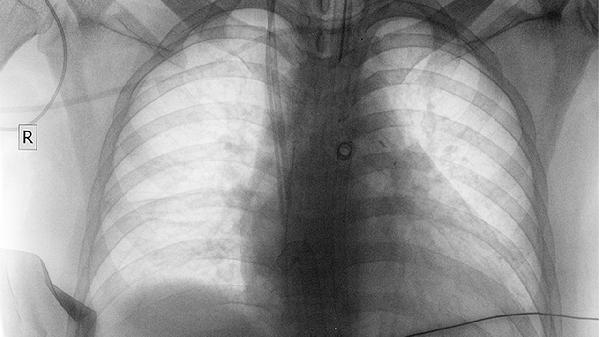

肺癌早期通過規(guī)范治療可實現臨床治愈,5年生存率可達80%以上。生存期受病理類型、分期、治療方式、患者體質、隨訪管理等因素影響。

術后前2年每3個月需進行胸部CT復查,監(jiān)測腫瘤標志物變化。戒煙可降低第二原發(fā)癌風險30%。長期生存者需關注放射性肺纖維化等遲發(fā)副作用。